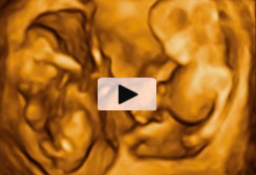

Los movimientos de estos gemelos de 12 semanas de gestación son extraordinariamente claros en la ecografía 4D. Los bebés mueven todo su cuerpo, especialmente brazos y piernas, adoptando multitud de posturas. Destaca el aspecto fieramente humano de los fetos, a pesar de su diminuto tamaño...

El movimiento de gemelos en el útero encierra sorpresas, como en esta ecografía 4D en la que vemos a dos hermanos en sus respectivas bolsas. El gemelo de la derecha parece estar bailando el "hula hoop" con su propio cordón umbilical, que le rodea las piernas formando un círculo. Destaca la...